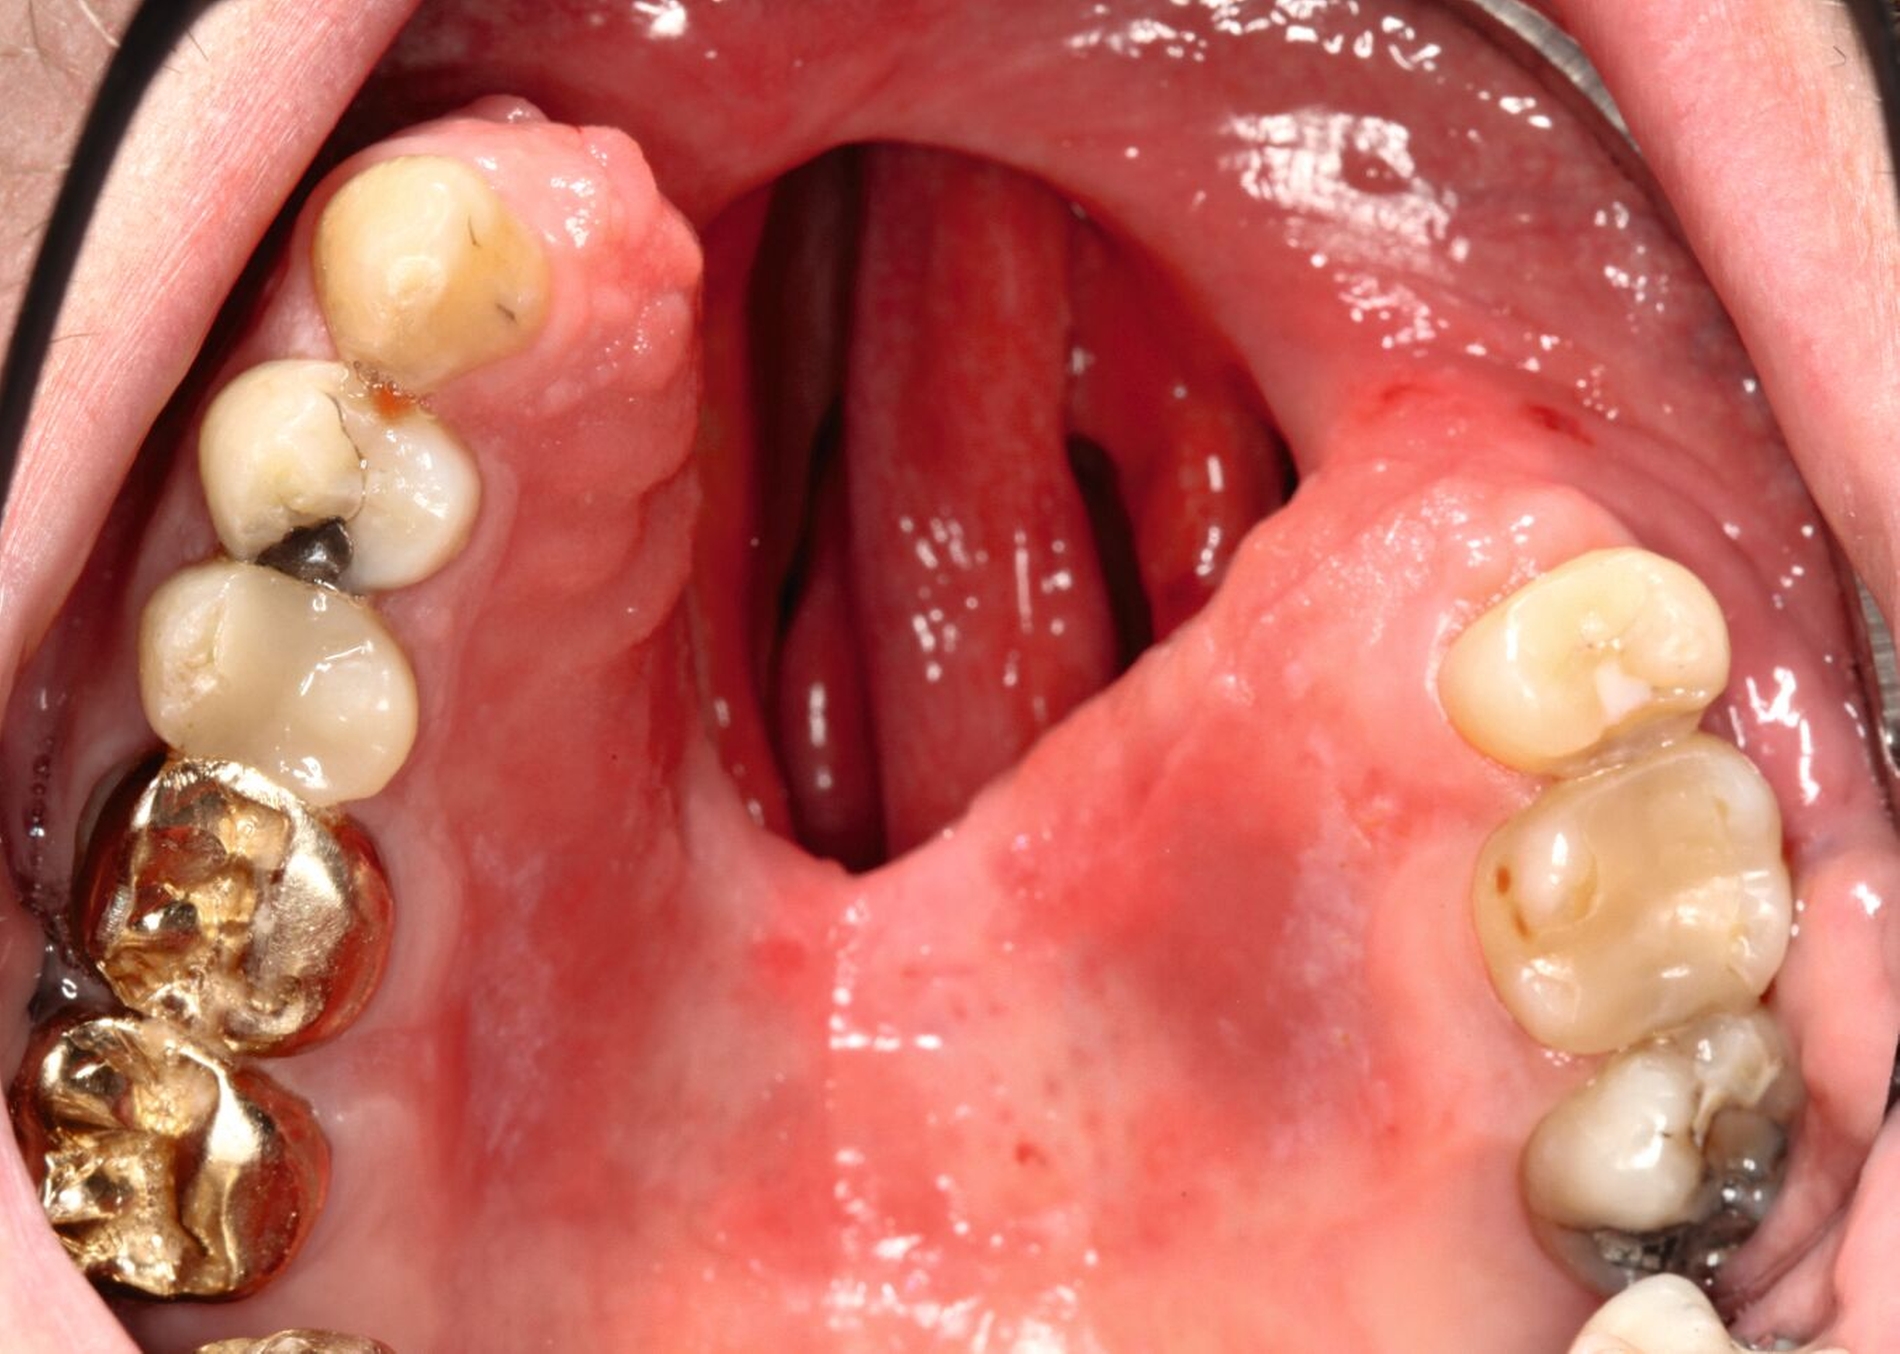

Bei einer Obturator-Prothese (Abbildung 2) erfolgt der Defektverschluss mittels hartem Acrylat-Prothesenkunststoff. Sie kann im Zenit offen oder geschlossen gestaltet sein. Der Halt wird über Klammern, Teleskope oder eine implantatgetragene Verankerung erzielt. Bei vollständiger Zahnlosigkeit ist eine Obturator-Prothese nicht zu empfehlen, da der gewöhnlich genutzte Saugeffekt nicht hergestellt werden kann. Bei zahnlosen Patienten, die keine Implantate erhalten können oder sollen, ist es sogar empfehlenswert, den Defekt nicht zu rekonstruieren, damit Unterschnitte für einen Silikon-Obturator genutzt werden können.

Die Handhabung und Reinigung einer Obturator-Prothese ist selbst bei kompromittiertem Geschick einfach und eine Unterfütterung ist wie bei einer herkömmlichen Prothese gut durchzuführen. Zu bedenken ist hier, dass der Patient funktionell stark eingeschränkt wird, wenn die Prothese im zahntechnischen Labor angepasst werden muss. Bei ausgedehnten Defekten kann eine Obturator-Prothese sehr groß werden. Dies erschwert bei eingeschränkter Mundöffnung oft die Eingliederung, weshalb hier gegebenenfalls geteilt werden muss. Eine Verbindung der Einzelteile kann über Riegel, Zapfen oder Magnete erfolgen. Bei bestrahlten Tumorpatienten ist das Entstehen von Druckstellen durch die Nutzung eines harten Prothesenkunstoffs ein Risiko, das beachtet werden muss.